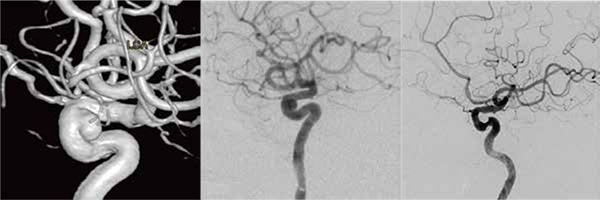

65 yo Male, diagnosed with a Ø5mm Right ICA wide neck aneurysm. Stent-assisted coiling achieved 55.8% packing density using 3 complex framing, 4 helical finishing, and 5 complex finishing coils.